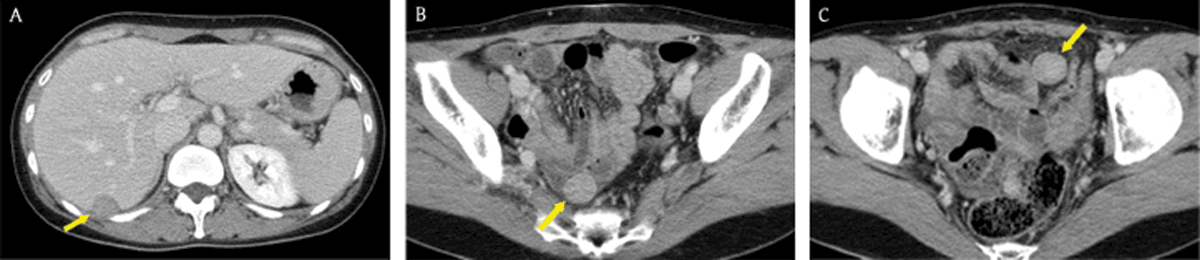

Figure 8

A 39-year-old woman whose surgical history included hysterectomy for uterine leiomyoma. Axial portal venous phase CT images showed multiple, well-circumscribed, solid masses (arrows) with mild-to-moderate enhancement in the peritoneal cavity. There were no abnormal lymph nodes, ascites, or omental haziness in the abdomen. The patient was diagnosed with leiomyomatosis peritonealis disseminata through percutaneous core needle biopsy under ultrasonography guidance.